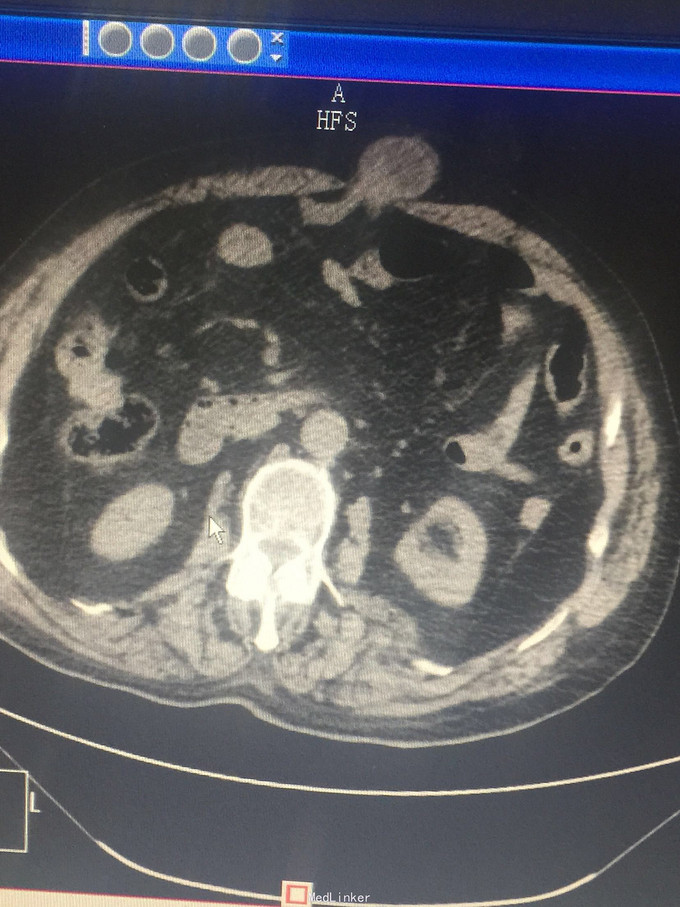

上腹部正中可复性包块10年不可还纳伴疼痛5小时

上腹壁见大小约5cm直径包块,压痛,质硬。

上腹部白线疝嵌顿,肠粘连,小肠嵌顿。肺炎。冠心病。白线缺损直径约4cm,急诊手术行上腹部白线疝嵌顿松解,小肠松解粘连,部分小肠还纳,白线疝补片修补术。